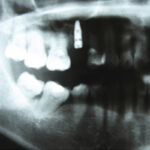

Osteopore (OSX) completed the first clinical trial for socket preservation in dental surgery.

First-in-human 3D printed patient specific implant with polycaprolactone-tricalcium phosphate (PCL-TCP) microarchitecture for mandibular reconstruction.

First mandible reconstruction with Osteomesh shaped tray to hold autologous bone grafts. Bony ingrowth and remodeling observed at 2 and 5 months postoperatively.